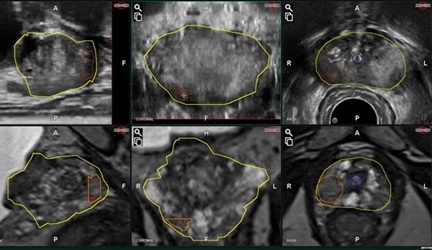

MRI超音波融合前立腺生検

前立腺生検は、前立腺を超音波で観察しながら、針を刺して組織を採取するものです。当院では生検の前にMRIを施行して、癌を疑う所見がないか確認して生検をしていましたが、MRIで所見があっても、超音波ではわからないことが多く、病変部を頭で思い描いて生検試行していました。しかし、実際に病変部が採取できているかは不確定でした。今回、2024年12月より富士フィルムヘルスケア社のMRI超音波融合生検システム「ARIETTA65(BiopSeeソフトウェア)」を導入しました。この装置によりMRI画像を超音波装置に取り込んで融合画像を作成して、MRI画像にて前立腺がんが疑われる部分を超音波上で狙って生検できるようになりました。これにより前立腺がんの診断精度が通常の生検より10-20%向上すると思われます。

![]() |

| ARIETTA65 | 上が超音波画像 下がMRI画像 |